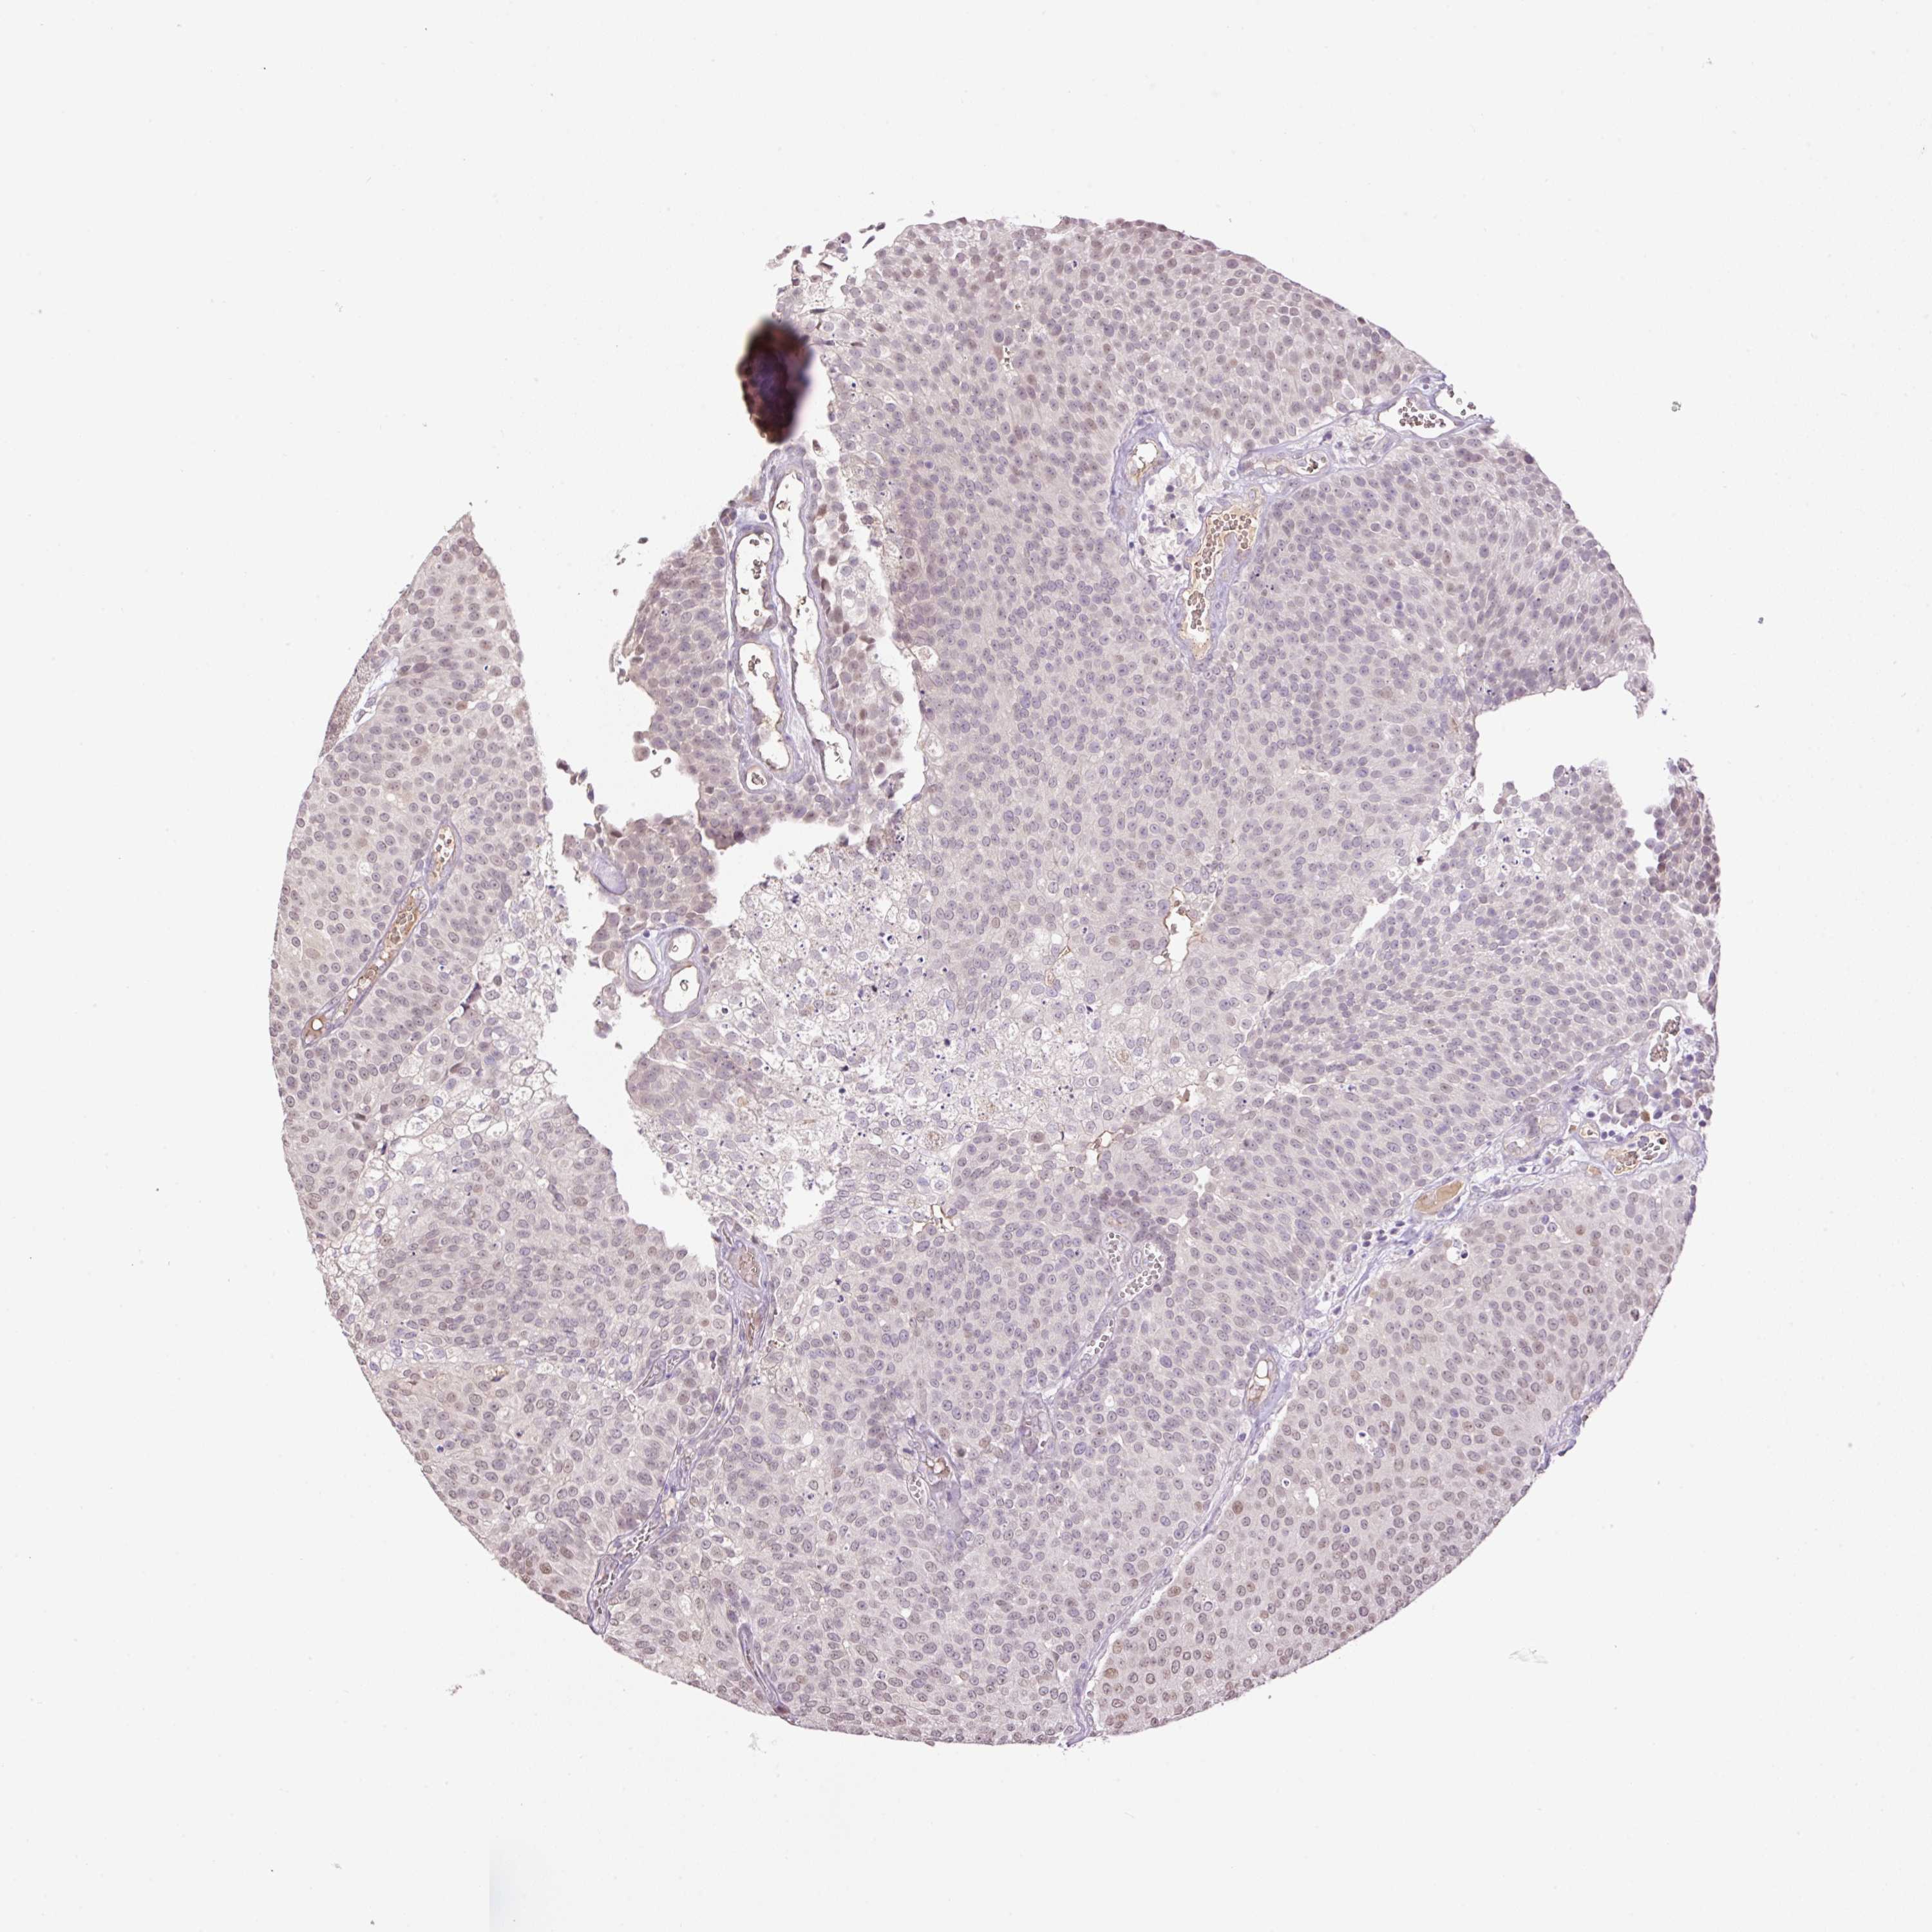

UROTHELIAL CANCER - Protein expressioni

A mouse-over function shows sample information and annotation data. Click on an image to view it in a full screen mode. Samples can be filtered based on level of antibody staining by selecting one or several of the following categories: high, medium, low and not detected. The assay and annotation is described here.

Note that samples used for immunohistochemistry by the Human Protein Atlas do not correspond to samples in the TCGA dataset.

Antibody stainingi

Antibody staining in the annotated cell types in the current human tissue is reported as not detected, low, medium, or high, based on conventional immunohistochemistry profiling in selected tissues. This score is based on the combination of the staining intensity and fraction of stained cells.

Each image is clickable and will lead to virtual microscopy that enables deeper exploration of all samples and also displays staining intensity scores, fraction scores and subcellular localization as well as patient and tissue information for each sample.

Antibody HPA055969

Antibody HPA062366

Staining

High

Medium

Low

Not detected

Intensity

Strong

Moderate

Weak

Negative

Quantity

>75%

75%-25%

<25%

None

Location

Nuclear

Cytoplasmic/membranous

Cytoplasmic/membranous,nuclear

Urothelial carcinoma, High grade

Urothelial carcinoma, NOS

Urothelial carcinoma, Low grade